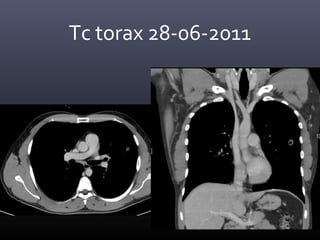

Tc torax 28-06-2011

• CONCLUSION TOMOGRAFICA:

• Nódulo pulmonar cavitado en el segmento 4 izquierdo con

afección de parénquima adyacente, lo cual como primera

posibilidad corresponde a Tuberculosis y diagnostico

diferencial de Coccidiodiomicosis.